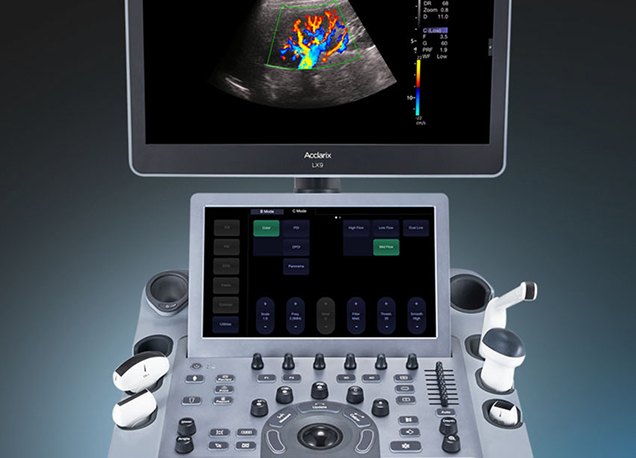

El EDAN Acclarix LX9 es el ecógrafo más avanzado de la línea Acclarix, diseñado para ofrecer diagnósticos veterinarios de ultra alta precisión.

Su tecnología de imagen de última generación proporciona detalle excepcional y máxima nitidez en estudios abdominales, reproductivos, musculoesqueléticos y cardiacos avanzados.

Desarrollado para entornos clínicos exigentes, combina calidad de imagen superior, herramientas inteligentes que aceleran el flujo de trabajo y una interfaz intuitiva que facilita la operación diaria. Su diseño integra especialización y versatilidad, garantizando rendimiento confiable en múltiples aplicaciones.

Diseño distintivo

Eficiencia avanzada en cada exploración

El EDAN Acclarix LX9 es un ecógrafo veterinario de alta gama que ofrece imágenes de ultra alta definición y diagnósticos precisos en estudios abdominales, cardiacos y musculoesqueléticos.

Su diseño ergonómico, pantalla amplia y flujo de trabajo intuitivo facilitan cada exploración, convirtiéndolo en una opción confiable y eficiente para clínicas y hospitales veterinarios.